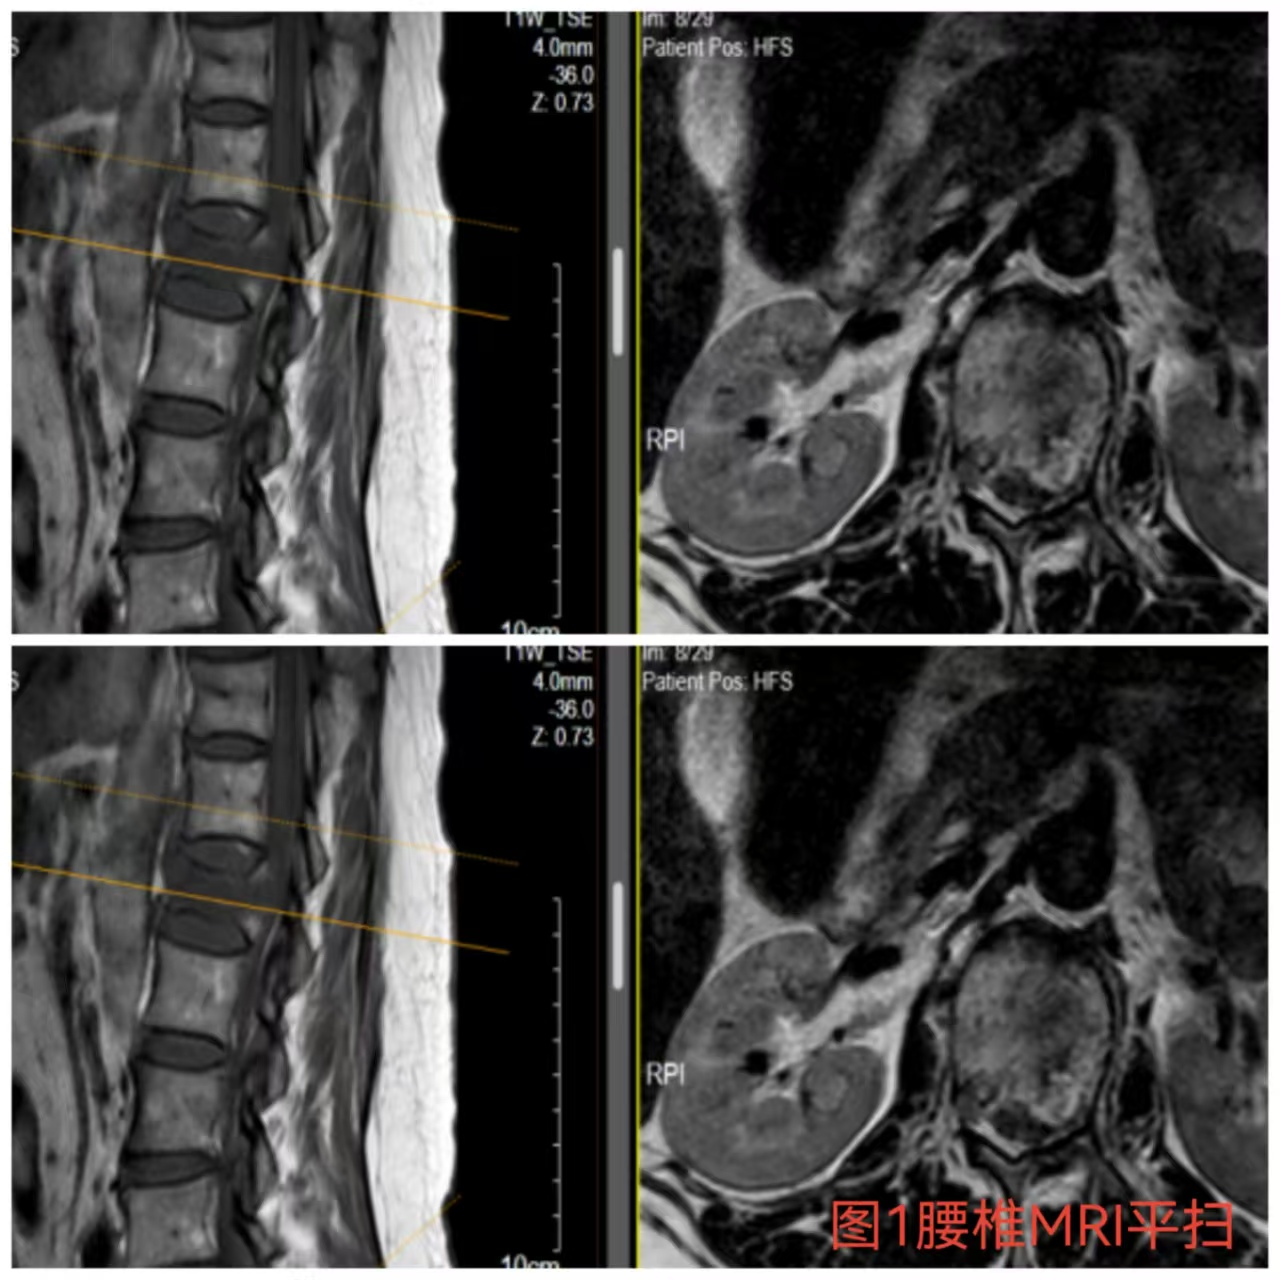

入院時(shí)患者躺在床上不能動(dòng)彈,眼神中透漏著深深的無(wú)助,對(duì)于她來(lái)說(shuō)這種傷情無(wú)疑是沉重的,尤其是腹股溝以下感覺(jué)消失、雙下肢肌力0級(jí),這意味著其下肢無(wú)法活動(dòng)及站立,仿佛被命運(yùn)按下了暫停鍵;與病人及家屬充分溝通病情后,第一時(shí)間給予對(duì)癥治療,監(jiān)測(cè)患者生命體征,行腰椎核磁檢查(圖1)提示:腰1椎體爆裂性骨折,椎體后緣塌陷致骨性椎管狹窄,壓迫脊髓神經(jīng),結(jié)合患者病情及輔助檢查可診斷為:“L1椎體爆裂性骨折伴雙下肢截癱”。